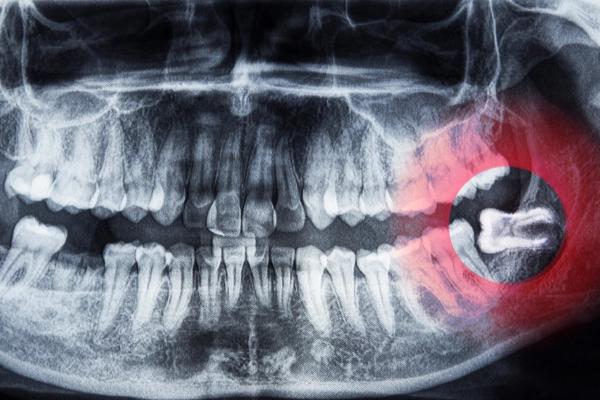

Nhổ răng khôn - An toàn, nhanh chóng với công nghệ Piezotome hiện đại

Răng khôn khi mọc lệch hoặc ngầm có thể gây đau nhức kéo dài, viêm nhiễm và ảnh hưởng đến các răng kế cận nếu không được xử lý kịp thời.

Nhờ ứng dụng công nghệ Piezotome kết hợp quy trình kiểm soát an toàn nghiêm ngặt, quá trình nhổ răng khôn tại Răng Hàm Mặt Hồng Ngọc được thực hiện nhẹ nhàng, hạn chế sang chấn mô mềm. Thời gian thực hiện nhanh chóng, trung bình khoảng 10 phút mỗi răng, giúp khách hàng hồi phục thuận lợi hơn sau điều trị.